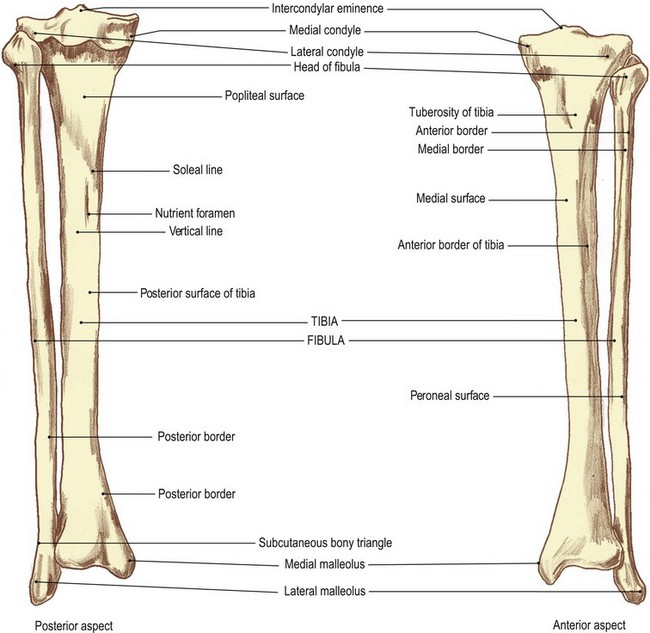

Anterior and posterior view of the tibia and fibula with labeling Stock …

celebrity hollywood cool: Tibia And Fibula Posterior

Radiographic positioning: Tibia Fibula

Tibia and Fibula Osteology of the Leg and Knee